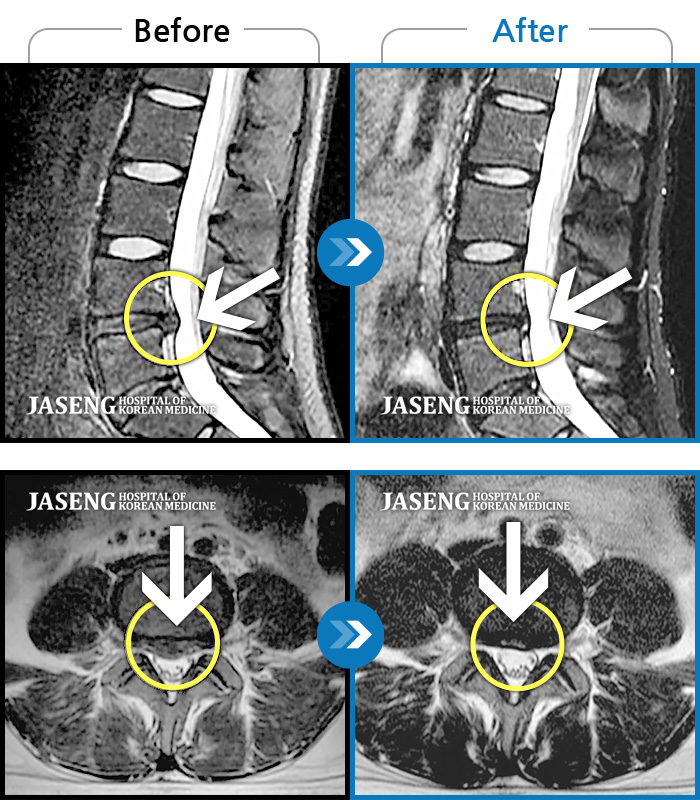

40대 초반 여성 환자인데요,, 처음 선생님 뵈었을 때에 1번,4,5번허리디스크 증상도 증상이지만,

본인 나이에 비해서 10~15년정도 퇴행이 많이 되어있어서 전체적으로 관리가 많이 필요하다고 설명해주셨구요,,

그당시 원장님진료실에서 보았던 저의 엠알아이사진이 아직도 생생히 기억이 납니다 ^^

뼈부분의 색이 왜저렇게 검냐고 여쭈어 보았더니, 말씀주신데로 "퇴행이"많이 되어서 그렇다고 설명해주시면서,,